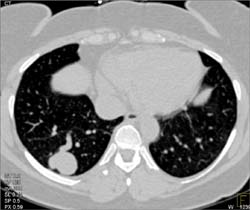

Sarcoma Involves the Mediastinum and Chest Wall